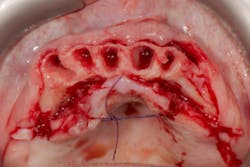

Placement of narrow implants. In a full-arch restoration in the presence of alveolae and thin ridges, narrow implants allow the placement of more biomaterial in the alveolae for ridge preservation. Bone grafting will be avoided in the presence of the ridges.